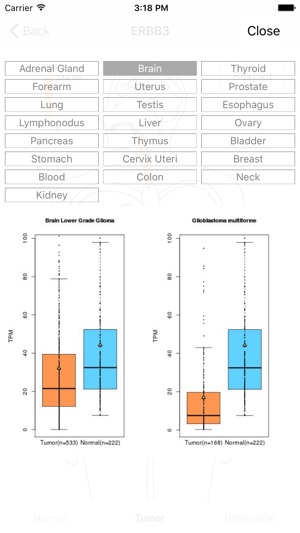

This GE-mini APP is designed to exhibit gene expression profiling of a given gene over many tissue types including tumors. The underlying data are based on RNA Sequencing results from both TCGA and GTEx after they are normalized and integrated. The current version, based on the September 2015 release of TCGA and the phs000424.v6.p1 release of GTEx, contains >19,000 total samples across 33 cancer types and 53 normal tissue types.